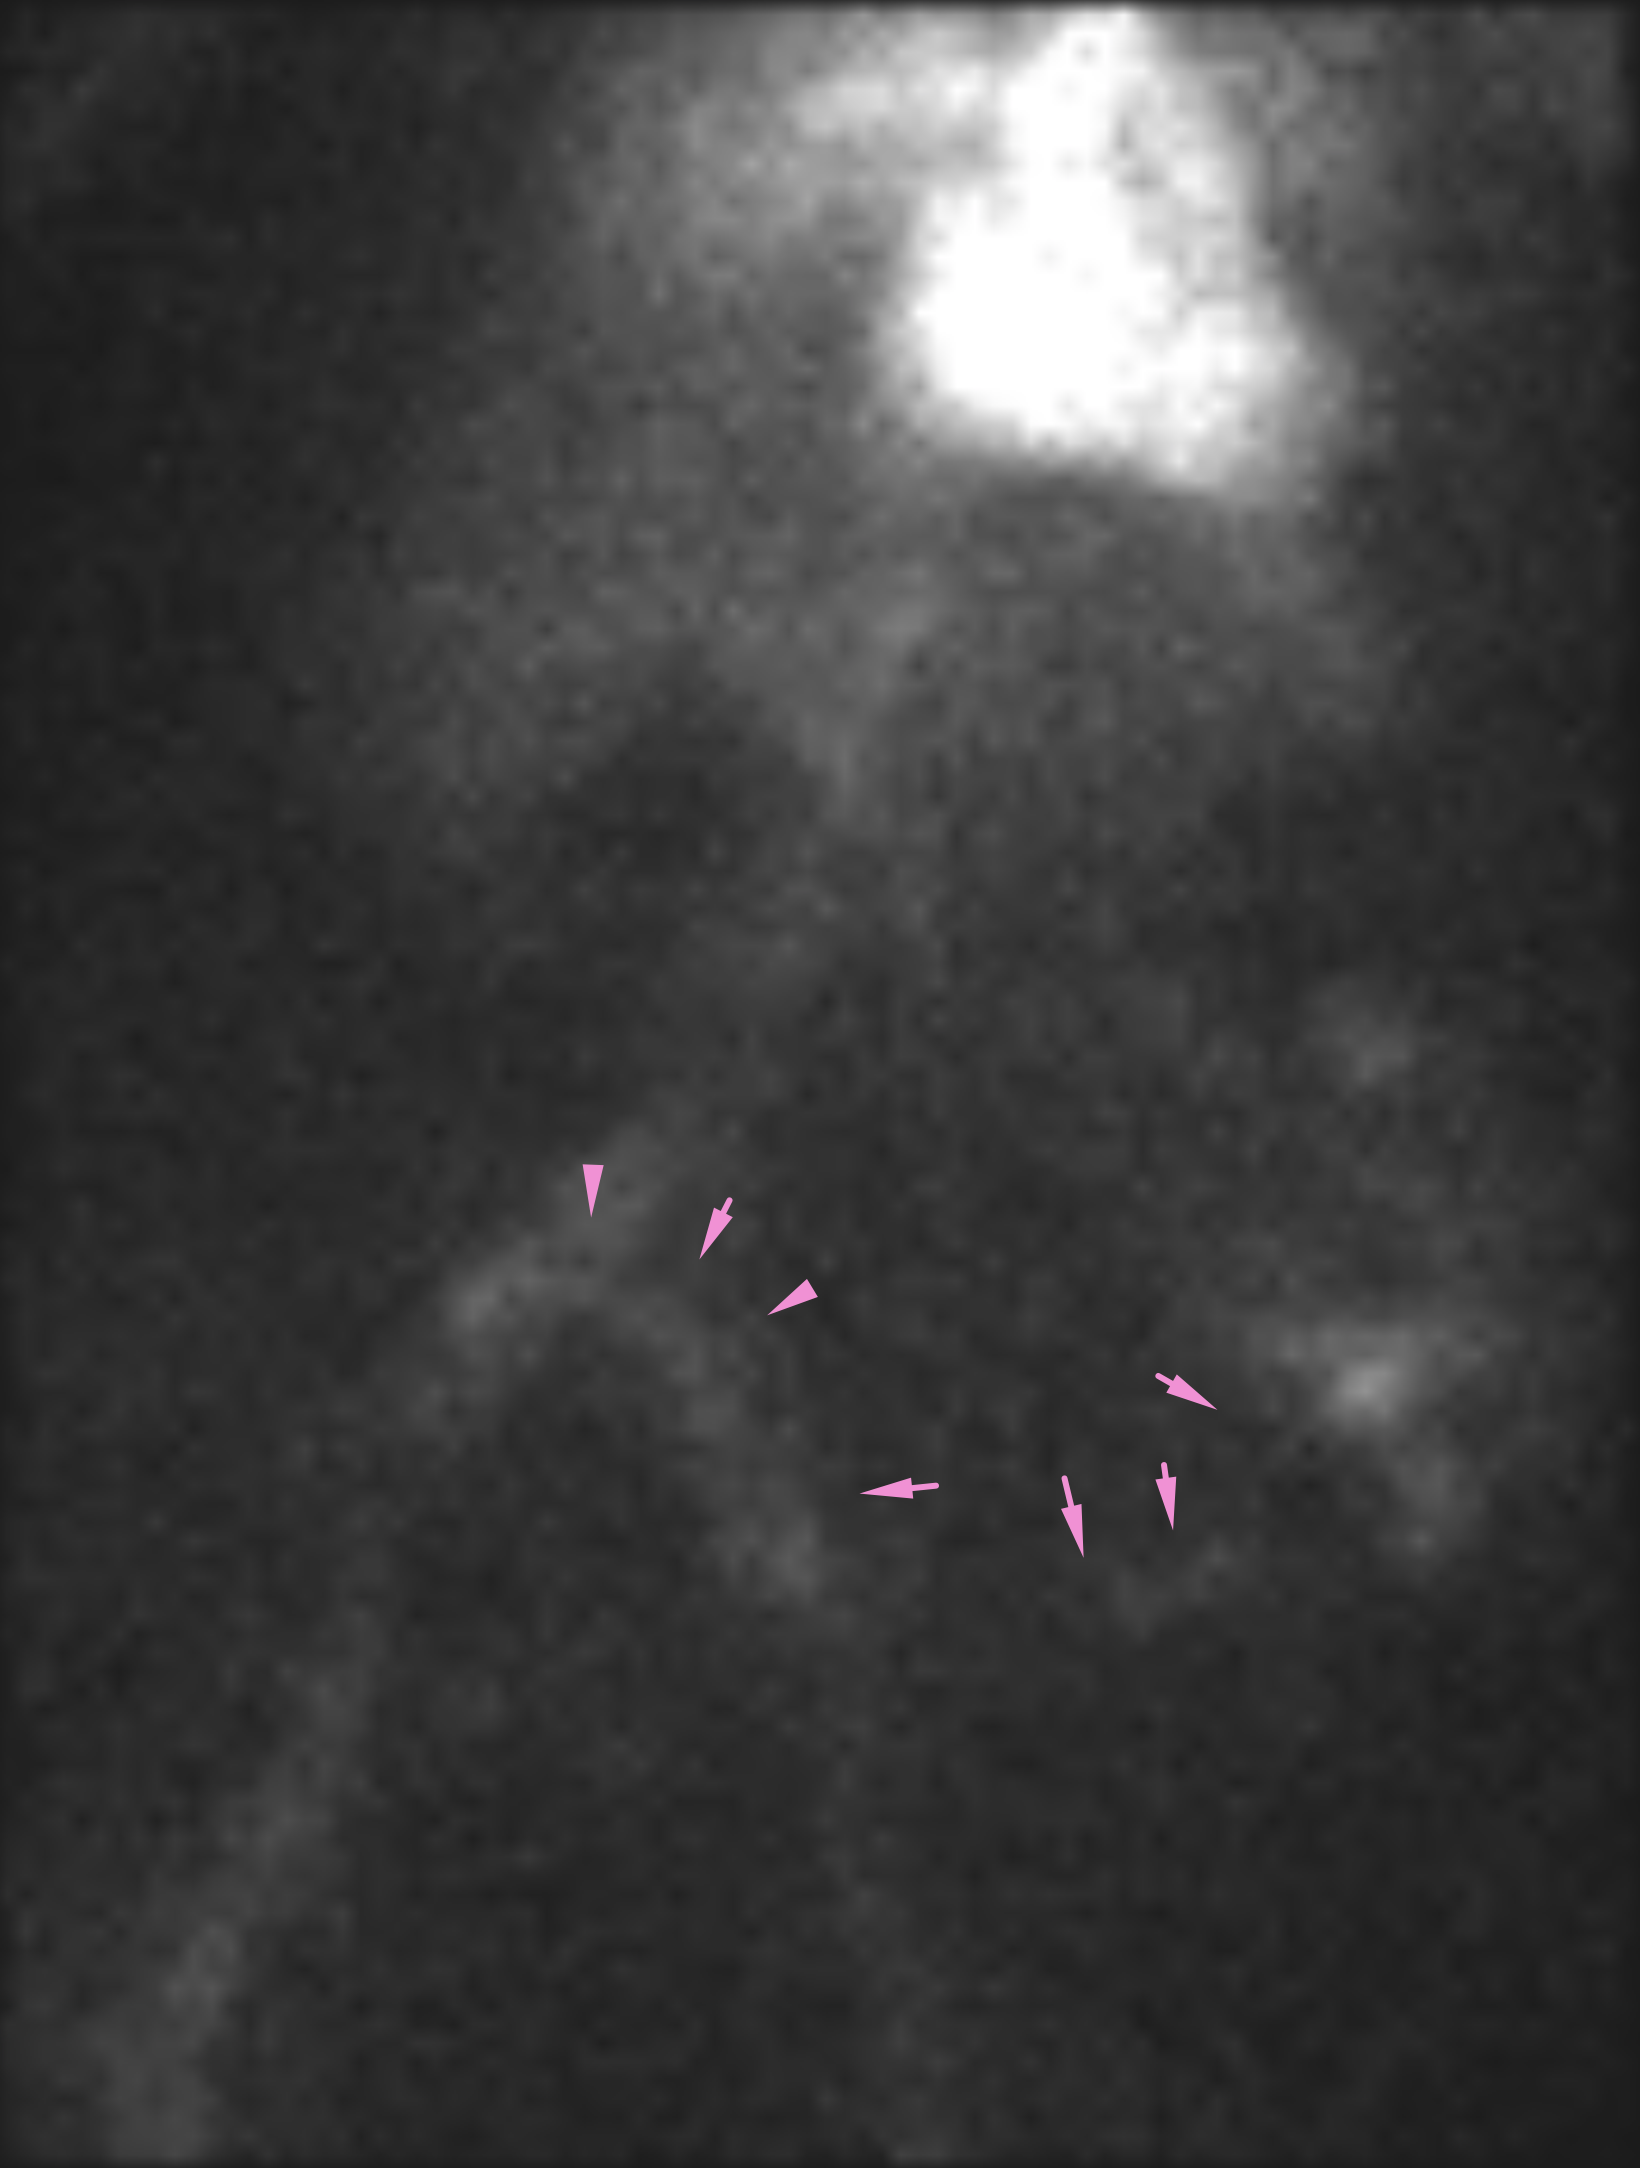

Age: 84

Sex: Female

Indication: Hematochezia with recent negative upper endoscopy and colonoscopy

Radiotracer: Tc99m labeled RBCs

Sample ReportPositive for active GI bleeding, likely originating within small bowel in the left lower quadrant.